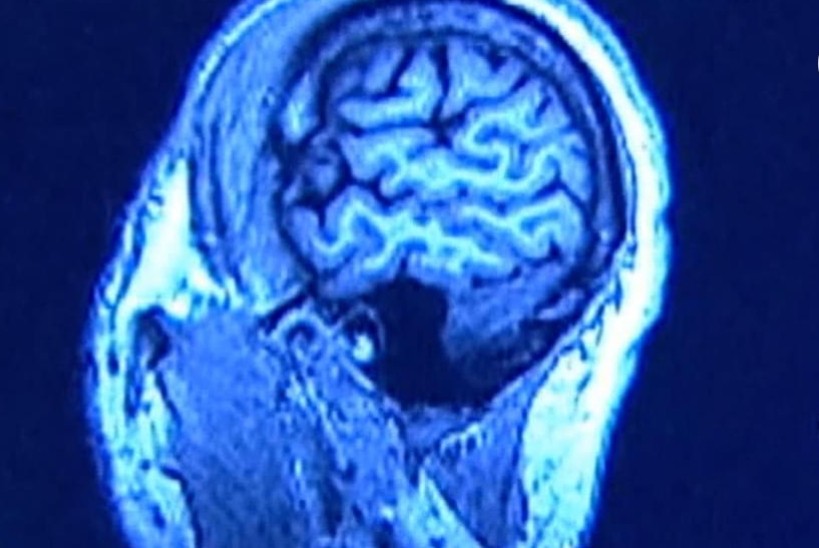

El deterioro cognitivo, descrito como “niebla mental”, puede persistir durante meses en los pacientes de covid-19, incluso en algunos que no fueron hospitalizados, según un nuevo estudio.

La investigación, publicada este viernes en la revista JAMA Network Open, descubrió que casi una cuarta parte de los pacientes de covid-19 en un registro del Sistema de Salud del Monte Sinaí experimentaron algunos problemas de memoria, y aunque los pacientes hospitalizados eran más propensos a padecer la llamada “niebla mental” después de una infección por coronavirus, algunos pacientes ambulatorios también sufrieron deterioro cognitivo.

El covid-19 está relacionado con el deterioro cognitivo y la aceleración de los síntomas del alzhéimer, según una investigación